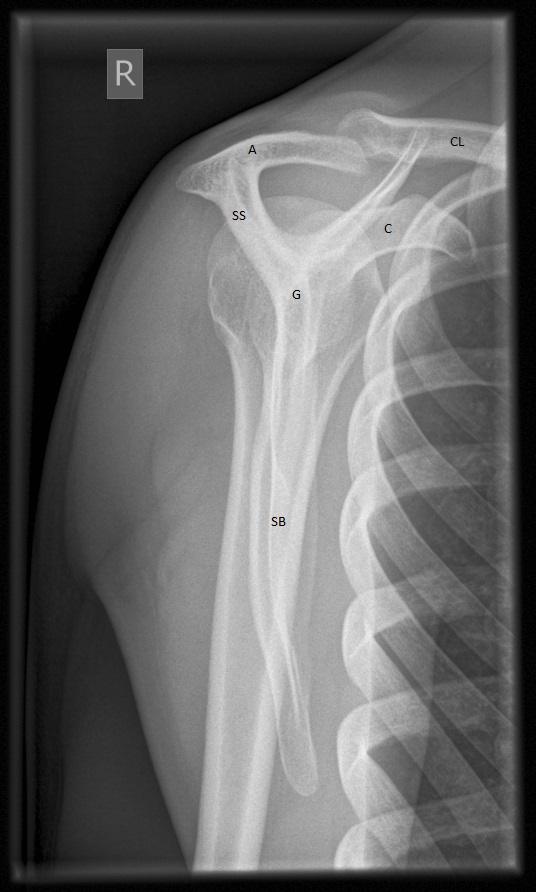

Trauma Shoulder X Ray Positioning . the shoulder series is fundamentally composed of two orthogonal views of the glenohumeral joint including. Y view true ap ap neutral. this view helps in visualizing potential fractures or dislocations to the proximal humerus and shoulder girdle in a trauma setting. Anterior dislocation is much more common than posterior.